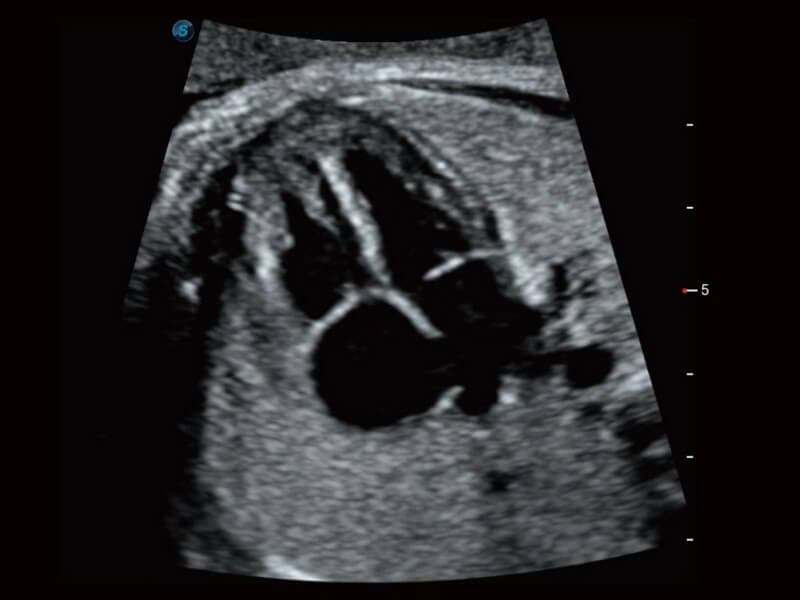

Die Bildqualität liegt immer im Zentrum definierter klinischer Ergebnisse. ELITE liefert eine leistungsstarke und klare Bildgebung, die durch eine leistungsstarke Architektur, hochmoderne Sonden und ausgeklügelte Verarbeitungsalgorithmen erzeugt wird, für ein höheres Maß an Klarheit und Vertrauen.

Basierend auf einem verlässlichen Deep-Learning-Algorithmus für Big Data ist S-Fetus eine brillante Komplettlösung für automatische Standard-Ebenen-Erfassung und Messung. Mit nur einem Klick werden gängige fetale Biometrie-Ergebnisse mit hoher Intelligenz, Genauigkeit und Effizienz erzielt, um einen beispiellosen Bedienungskomfort zu gewährleisten.

Dank der Unterstützung von Auto OB wird eine schnelle und hoch effiziente fetale Biometrie erreicht. Gleichzeitig kann diese auf Deep Learning basierende Methode zu konsistenteren Ergebnissen führen und die Variabilität, die vom Anwender abhängig ist, effektiv reduzieren.